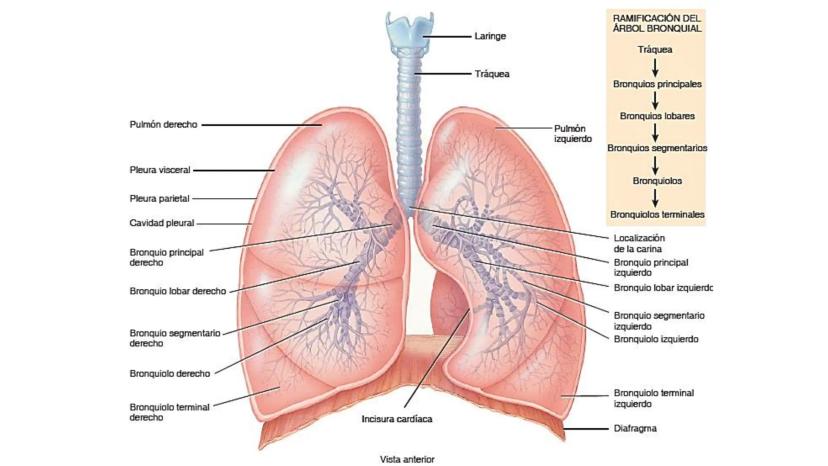

Conceptos importantes sobre el sistema respiratorio.